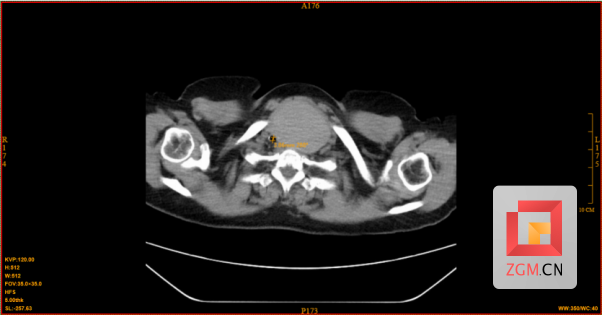

今年66岁的何阿姨,因“喘息、呼吸困难”就诊于呼吸与危重症医学科。经影像学检查发现,其甲状腺左叶存在一个约6.8cm的囊实性肿物,气管明显受压右移,最窄处仅约3.86mm,狭窄程度超过70%,同样面临极高的窒息风险。